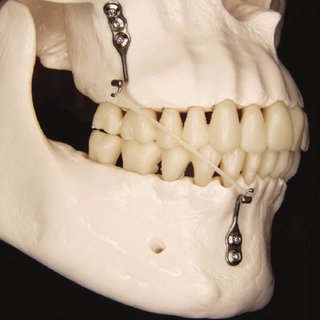

Fogszabályozási minilemez

A fogszabályzási minilemez célja hasonló a fogszabályozási miniimplantátumokéhoz. Betonbiztos horgonylati megoldás, mely során a csont felszínén 2-4 minicsavarral rögzítünk egy kisméretű lemezt. A minilemez, mivel sok csavarral rögzül, jóval stabilabb, mint az egyszerű fogszabályozási miniimplantátum. Nagy hátránya, hogy mind a behelyezése, mind az eltávolítása helyi érzéstelenítésben végzett műtéttel zajlik, ami megterhelő lehet pácienseim számára. A műtét kb. hasonlóan zajlik, mint egy fogimplantátum behelyezésénél. A műtét technikai nehézségei miatt ára is sokszorosa a miniimplantátumokénak. Kiválóan végezhető minilemezek segítségével teljes alsó és/vagy felső fogív hátravitel, felső fogív felfelé mozgatása (ínymosoly esetén).